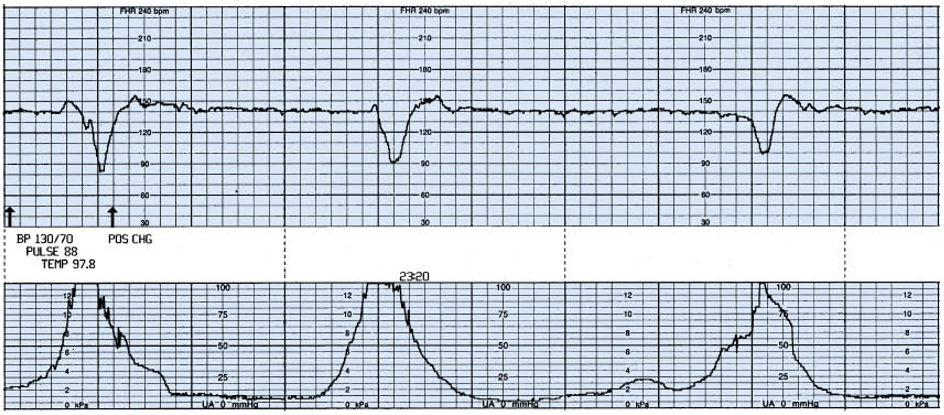

34세의 임신 38주 초산모가 5시간 전부터 규칙적인 진통이 있어 내원하였다. 혈압은 130/80 mmHg, 맥박은 88회/분, 호흡수는 18회/분, 체온은 37.7도이다. 초음파 검사에서 태아는 두위, 예상 태아몸무게 3000g, 양수 지수는 4cm로 나타났다. 골반 검사상 자궁경부 7cm 확장, 80% 소실, 태아 하강도 0이다. 전자태아심박동-자궁수축감시검사 결과이다. 처치는?

Imp: variable deceleration

• 38주 초산모가 규칙적인 진통으로 내원했다. 양수지수가 4cm로 양수과소증을 보이고 있고 NST상에서 variable deceleration을 보이고 있다. variable deceleration에서 cord prolapse가 없다면(골반진찰상 cord compression이 있다고 따로 적어두지 않아 없는 것으로 보인다) 우선적으로 체위변경, 산소 공급 등의 조치를 취할 수 있다. 계속해서 variable deceleration이 recurrent하게 발생한다면 양수주입술도 고려해볼 수 있다.

• NST의 큰 한칸은 1분이다. 작은칸 3개가 30초이므로 onset to nadir가 30초 미만의 variable deceleration인 것을 알 수 있다.

• 2017년 ACOG에서 양수주입술은 양수과소증으로 인한 cord compression으로 "repetitive" variable deceleration이 발생하면 고려해볼 수 있다고 하였다. Uptodate에선 양수과소증으로 인한 cord compression에서 recurrent variable deceleration이 나타나면 second line으로 양수주입술을 고려해볼 수 있다고 한다.